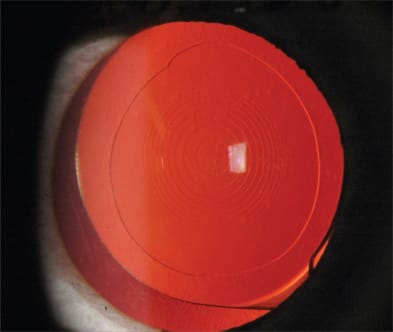

The development of PCO (Figure 1) varies with different IOL composition and interferes with the vitreoretinal examination preoperatively and intraoperatively. Even though an opacified posterior capsule can be remedied with a YAG laser or an intraoperative central capsulectomy, an open posterior capsule alters the way a vitreoretinal surgeon may approach and manage various scenarios during vitreoretinal surgery. PCO is most common with silicone IOLs.1-7 Silicone stimulates the production of collagen precursors and extracellular matrix by anterior subcapsular epithelial cells, leading to PCO. The rate of PCO is significantly lower with hydrophobic IOLs,8-12 which become coated with fibronectin, a naturally occurring bioadhesive, soon after implantation. This facilitates adherence to the capsule, isolating it from the immune system, resulting in less inflammation and opacification.

Figure 1. Posterior capsular opacification (PCO) highlighting Elschnig pearl formation following placement of multi-piece multifocal hydrophobic acrylic posterior chamber intraocular lens.